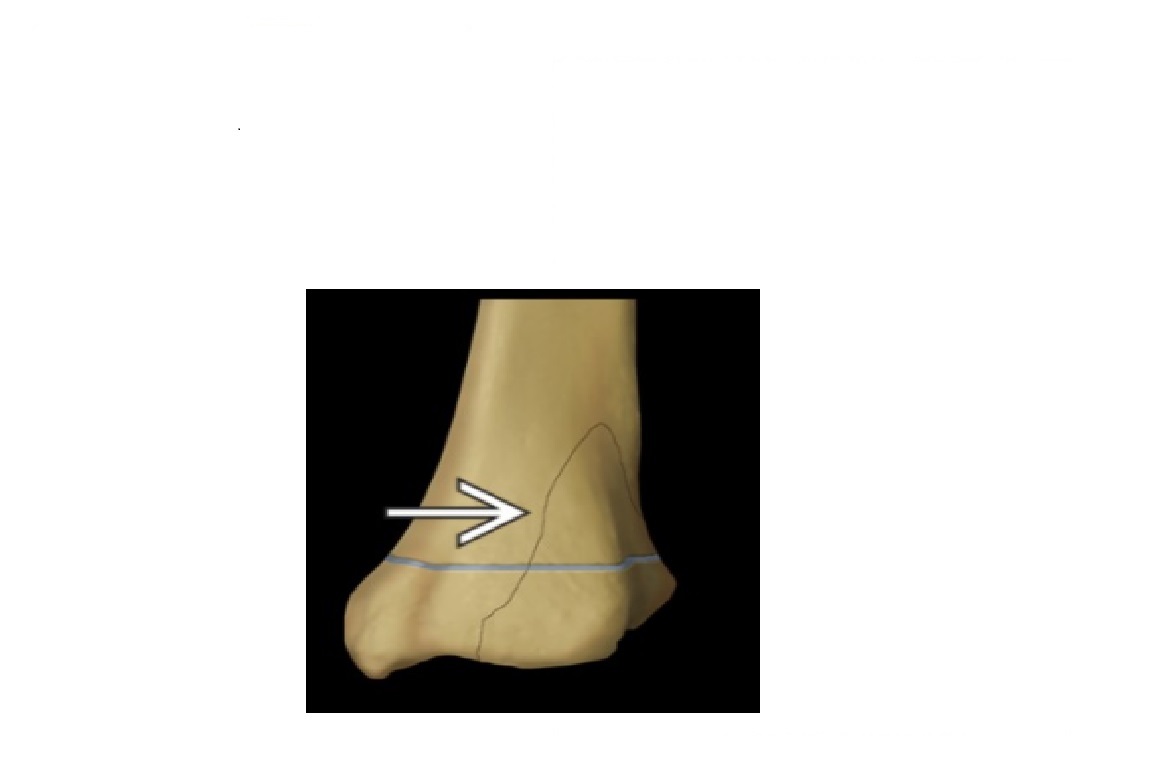

18

Q

What is Maisonneuve fracture?

A

Medial tibial malleolus with disruption of the distal tibiofibular syndesmosis.

most X ray and look at the proximal fibula = # proximal fibular

How well did you know this?

1

Not at all

2

3

4

5

Perfectly